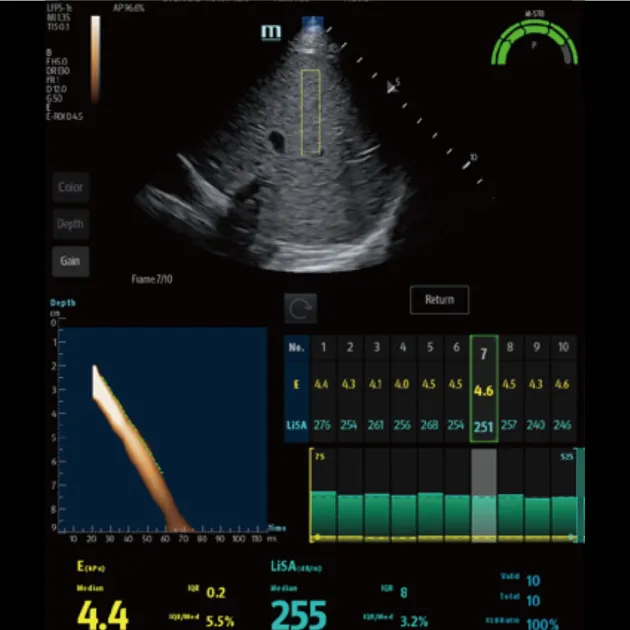

Количественный анализ ригидности печени Обеспечивает количественное определение жесткости печени и стадии фиброза печени с помощью технологии переходной эластографии

Количественный анализ стеатоза печени Количественная оцененка тяжести стеатоза печени с помощью технологии LiSA (поглощения ультразвука в печени).

Advanced ViTE (визуализированная транзиторная эластография)

- Проводить количественное выявление и оценку фиброза и стеатоза печени под визуальным контролем 2D-ультразвука в режиме реального времени

Быстрое интеллектуальное получение данных Q-сканирования

- Нажатием одной кнопки можно автоматически и непрерывно получать 10 групп эффективных данных и проводить интеллектуальный анализ

- Точные и достоверные результаты обнаружения могут быть получены немедленно, всего через 7 секунд после позиционирования

Надежный показатель контроля качества

- Индекс давления (P): качественный контроль давления зонда

- Индекс стабильности движения (m-STB): обеспечивает стабильность дыхания

- Четкая индикация с другим цветом для улучшения контроля качества во время обследования